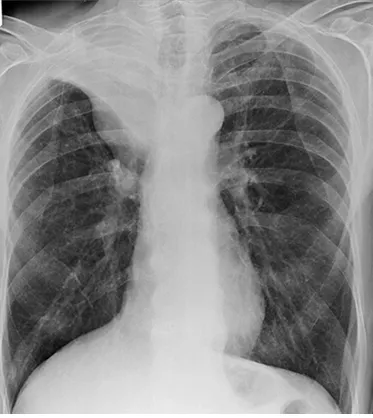

62세 남성이 기침과 함께 피를 뱉는 증상을 호소하며 병원을 찾았다. 그는 35갑년의 흡연력이 있으며, 최근 3주 동안 지속된 기침과 가래 증상을 경험했다. 혈압은 120/80mmHg, 맥박은 76회/분, 호흡수는 20회/분, 체온은 36.8°C로 측정되었다. 가슴 X선 사진을 찍었다. 이 환자에게 필요한 다음 단계 검사는 무엇인가?

35갑년의 흡연력과 지속적인 기침, 가래, 객혈 증상으로 폐암을 의심할 수 있다.

• Golden S sign이 우상엽에서 관찰된다. 일반적으로는 Bronchus를 막고 있는 central mass가 있는 경우 나타나는 X선 소견이다. 다음 시행할 검사로는 선택지 중 Bronchogenic mass를 확인하기 위한 기관지내시경이 가장 정답에 가깝다.

(3) 무기폐(atelectasis): Golden S sign 등

우상엽에 보이는 공동(cavity) | 우상엽의 무기폐(atelectasis)로 인해 보이는 golden S sign |